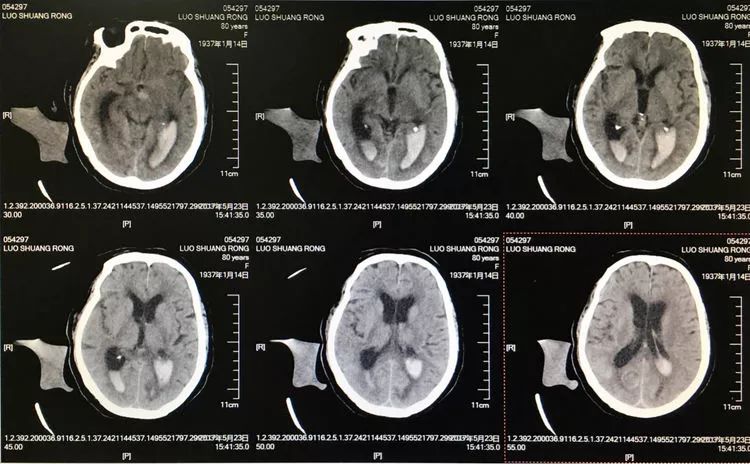

患者女性,80岁,以SAH于2017.5.20急诊入院,CTA示基底动脉顶端动脉瘤。

2.17.5.27 DSA+栓塞